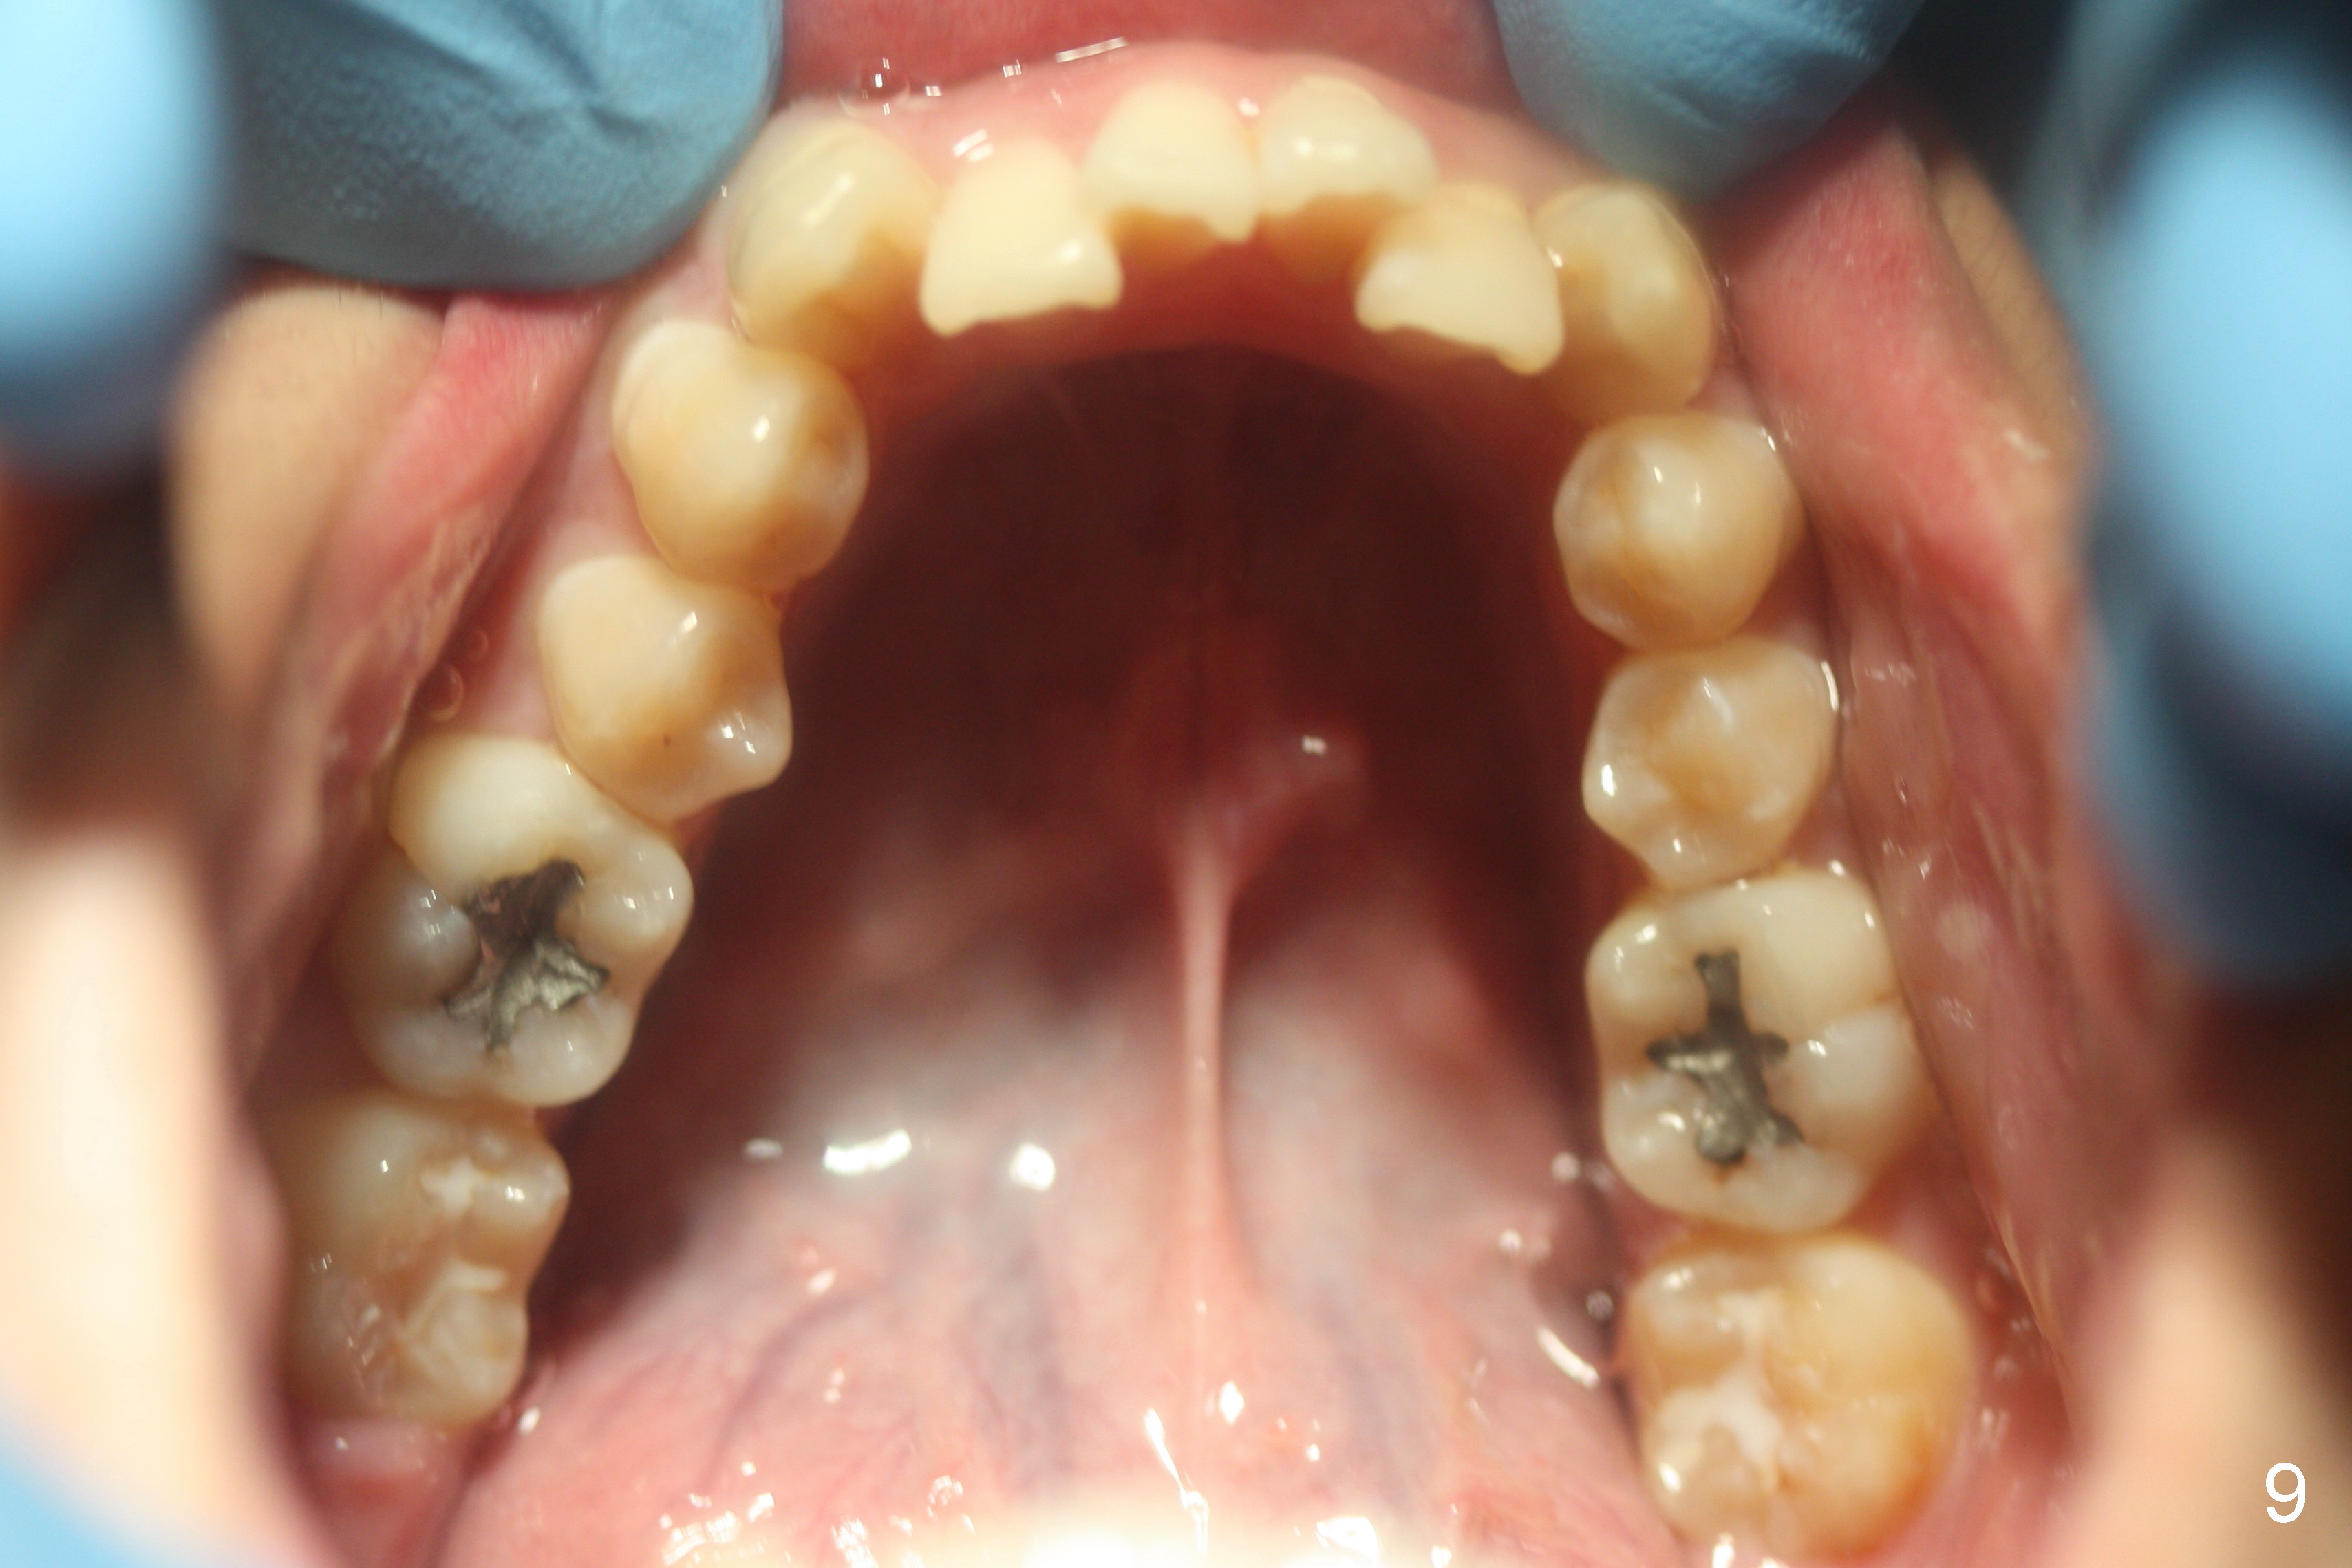

A 15-year-old man wants to improve the facial appearance.

Xin Wei, DDS, PhD, MS 1st edition 02/27/2017, last revision 09/09/2018